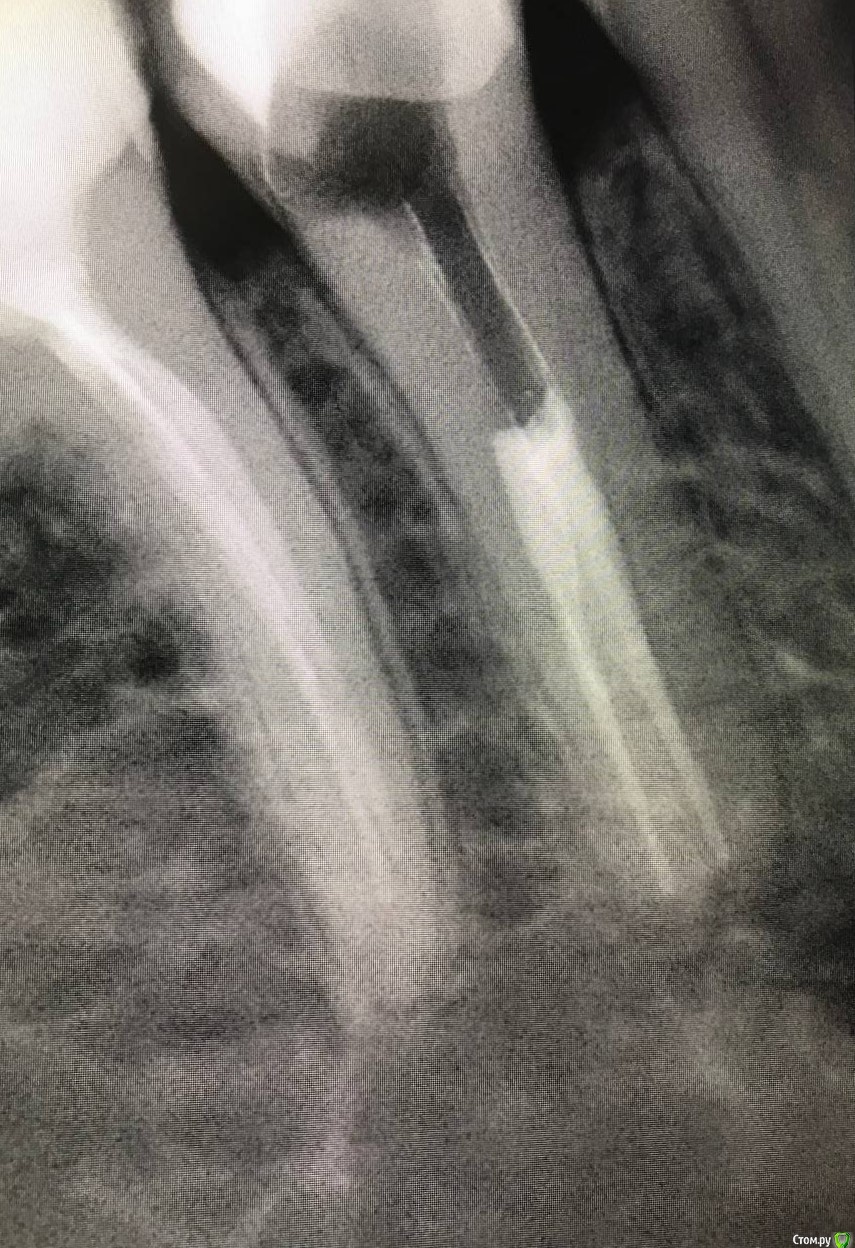

1586Doc Опубликовано 8 февраля, 2020 Поделиться Опубликовано 8 февраля, 2020 5 месяцев назад обратилась пациентка с симптоматикой периодонтита. Оценили, попробовали. Пломбировка вертикалка. 5 месяцев и контроль, боли нет, подвижности тоже. 2 Ссылка на комментарий

1586Doc Опубликовано 10 февраля, 2020 Автор Поделиться Опубликовано 10 февраля, 2020 (изменено) А где контроль на сегодня? При таком качестве снимков оценить будет тяжело.первые 2 фото снимки 9 месяц назад, до ревизии Изменено 10 февраля, 2020 пользователем 1586Doc Ссылка на комментарий